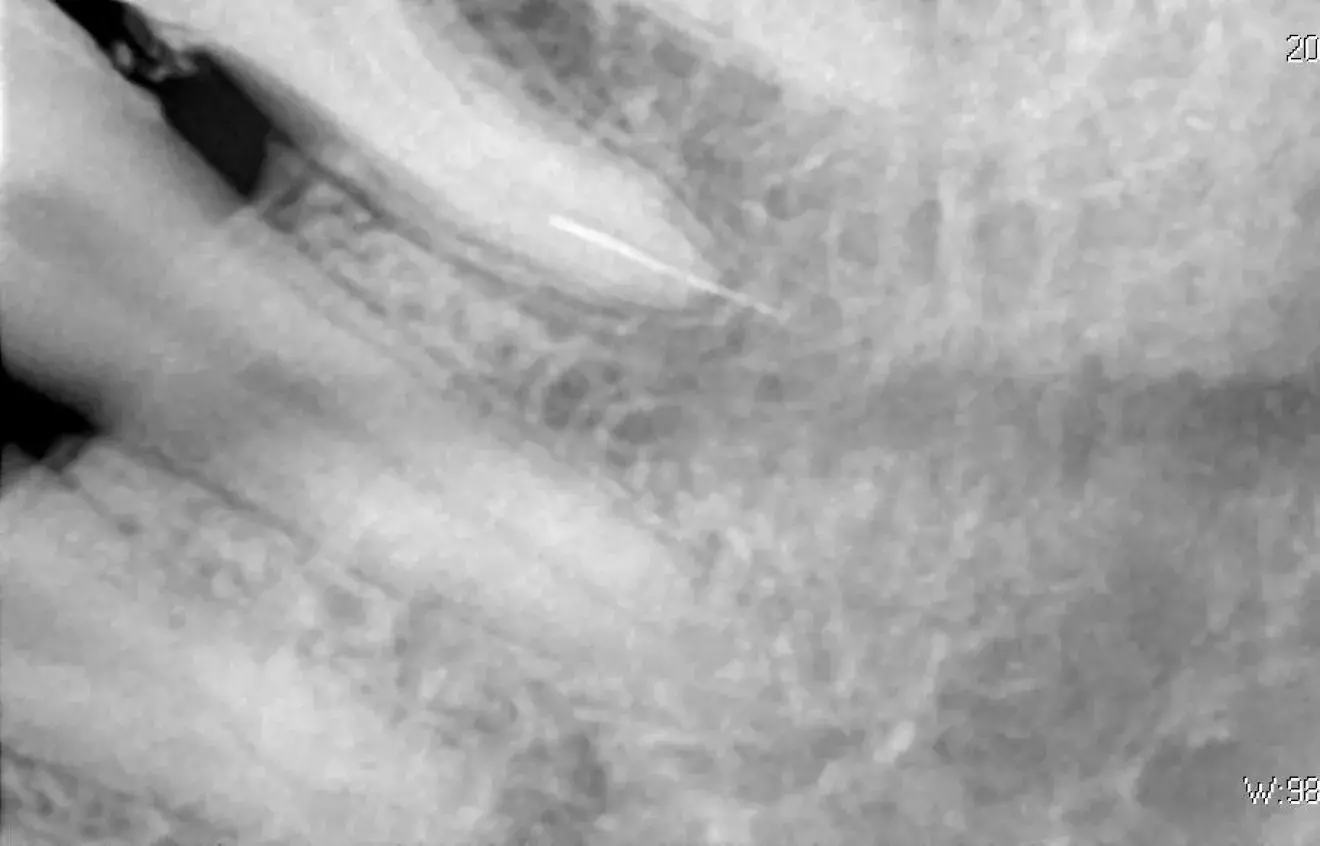

Без мікроскопа вилучити інструмент майже неможливо. Збільшення в 15-20 разів і потужне фокусоване світло дозволяють лікарю бачити кінець уламка та працювати з мікроскопічною точністю.

- Лікар обережно розширює верхню частину каналу, щоб створити прямий візуальний доступ до уламка.

- Використовуються дуже тонкі ручні інструменти або спеціальні ультразвукові насадки.

- Ультразвук: Спеціальні мікронасадки створюють вібрацію, яка змушує уламок «викрутитися» з каналу. Часто це працює, якщо інструмент застряг у прямій частині.

- Петльові техніки (наприклад, петля Террі): За допомогою тонкого дроту або спеціального інструмента на кінець уламка накидається мікропетля, яка затягується і дозволяє витягти його.